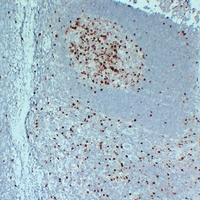

(Immunohistochemical analysis of Topoisomerase 2 alpha staining in human tonsil formalin fixed paraffin embedded tissue section. The section was pre-treated using heat mediated antigen retrieval with sodium citrate buffer (pH 6.0). The section was then incubated with the antibody at room temperature and detected using an HRP conjugated compact polymer system. DAB was used as the chromogen. The section was then counterstained with haematoxylin and mounted with DPX.)